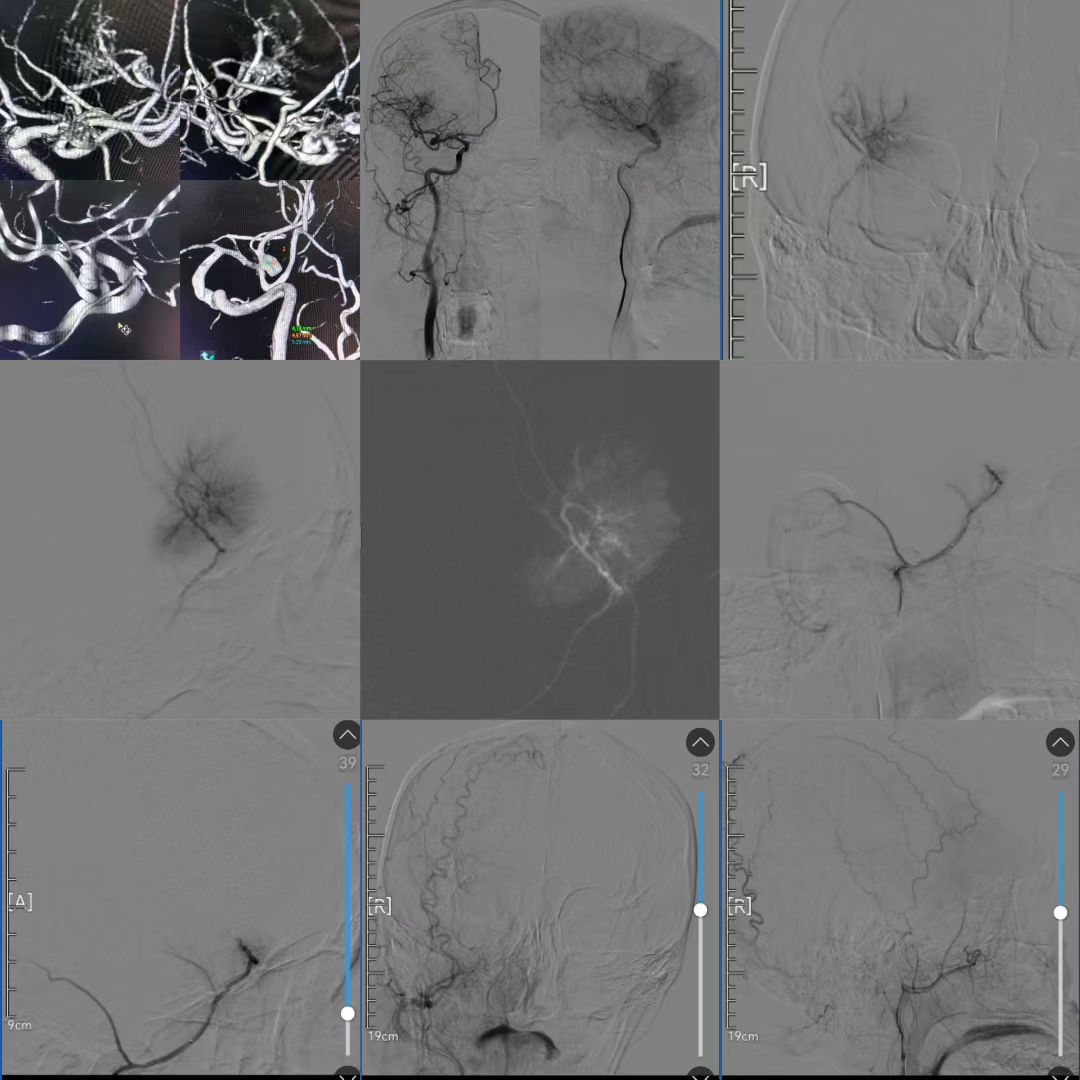

面对这样的情况,团队陷入了沉思。如果选择分期手术,佟先生将面临二次开颅的风险;若强行同期切除,术中大出血可能出现致命危险。经过严谨的术前讨论,团队最终决定采用“双管齐下”策略,先行数字减影血管造影(以下简称DSA)下脑膜瘤供血动脉栓塞,精准阻断肿瘤“输血管”,然后再行脑膜瘤切除并同期夹闭动脉瘤。

术前DSA造影证实脑膜瘤血供丰富

与颅内动脉瘤关系密切

栓塞动脉瘤供血动脉